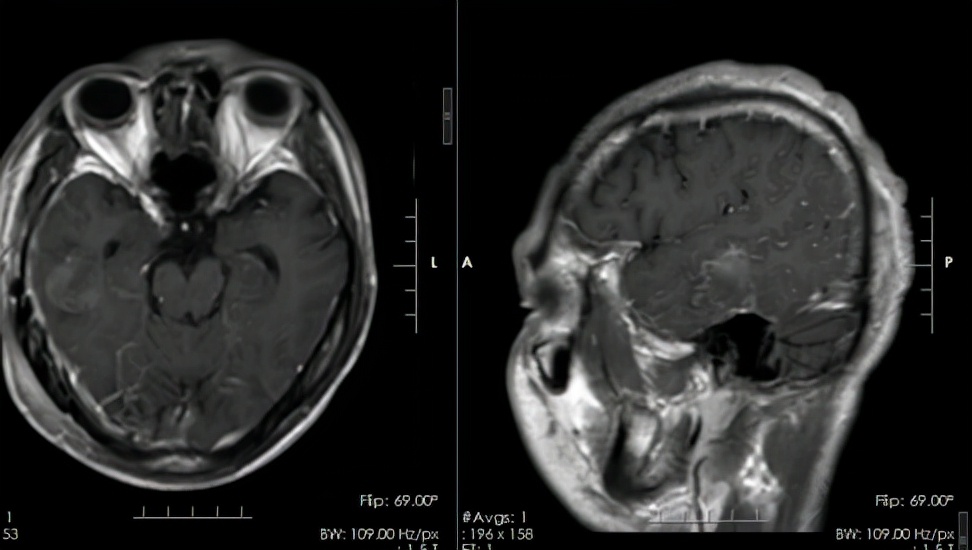

术后,患者恢复良好,术后病理结果:结合临床及影像,符合(右侧颞叶)血管畸形,伴出血。张先生住院治疗一段时间后再次顺利出院。

术后头颅MRI:右侧颞叶海绵状血管瘤切除术后